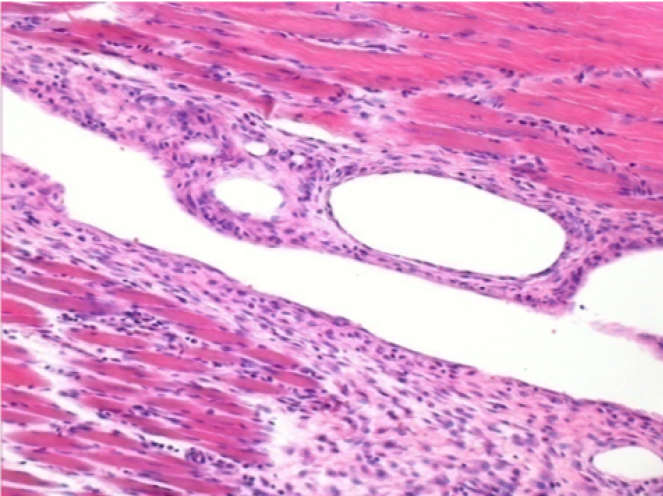

سبعة أشهر بعد حقن إندوبيل

7 أشهر (D210) بعد حقن Endopeel IM 0.1 مل في العضلة أمام الظنبوب اليمنى.

Complete Restitutio ad integrum after 7 months

L : Control-100xD210

R:100xD210

L :Control 50xD210

R50X-D210